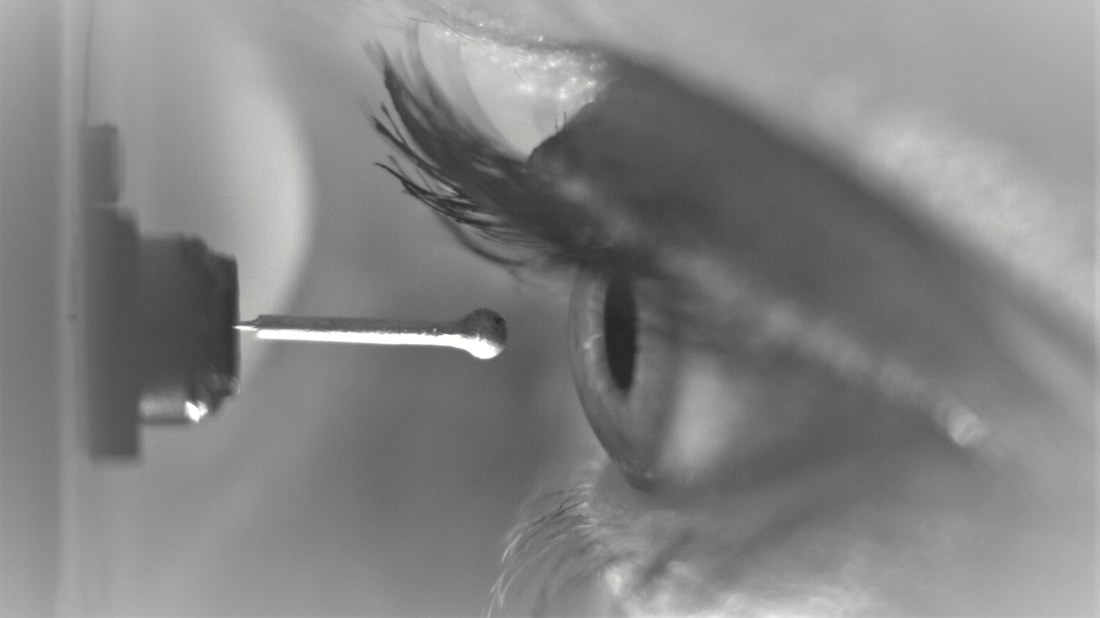

• Aesthesiometer for measuring corneal sensitivity

Feasibility study for the development of an aesthesiometer.